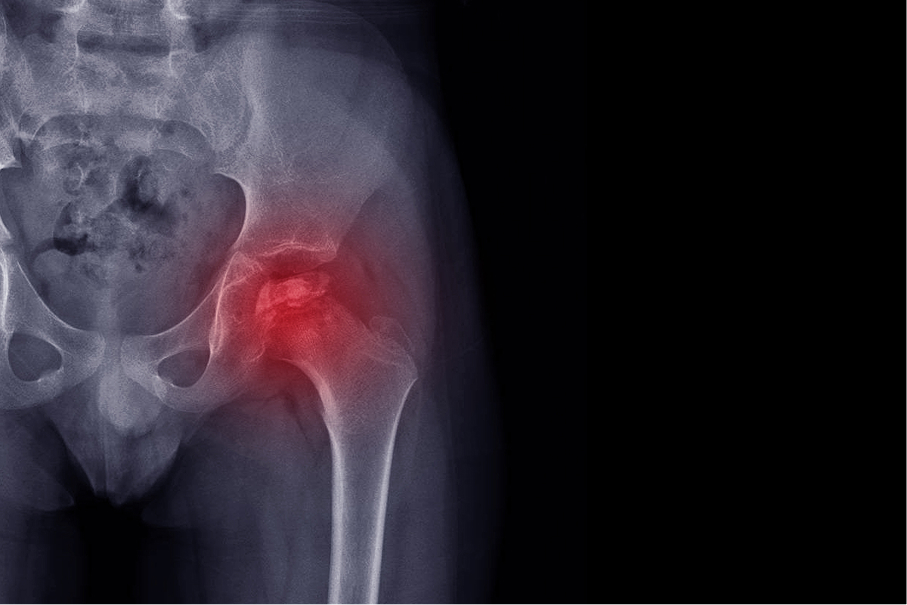

Legg-Calve-Perthes Disease of the hip

Legg-Calve-Perthes Disease of the hip is a chronic and often progressive condition. If left untreated, it can lead to long-term pain and disability. Unfortunately, there is no consensus on which treatment or treatments are best. This has long been a source of confusion and frustration for patients, their families and their providers, alike.